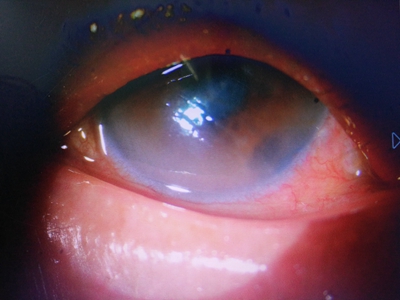

角膜挫伤角膜水肿变浑浊图

角膜挫伤表现为角膜有水肿增厚的现象,由原本的清澈、透明变为部分浑浊,颜色发白,同时有较多红血丝,考虑是感染导致,患者应积极采取治疗,以免疾病进一步发展。